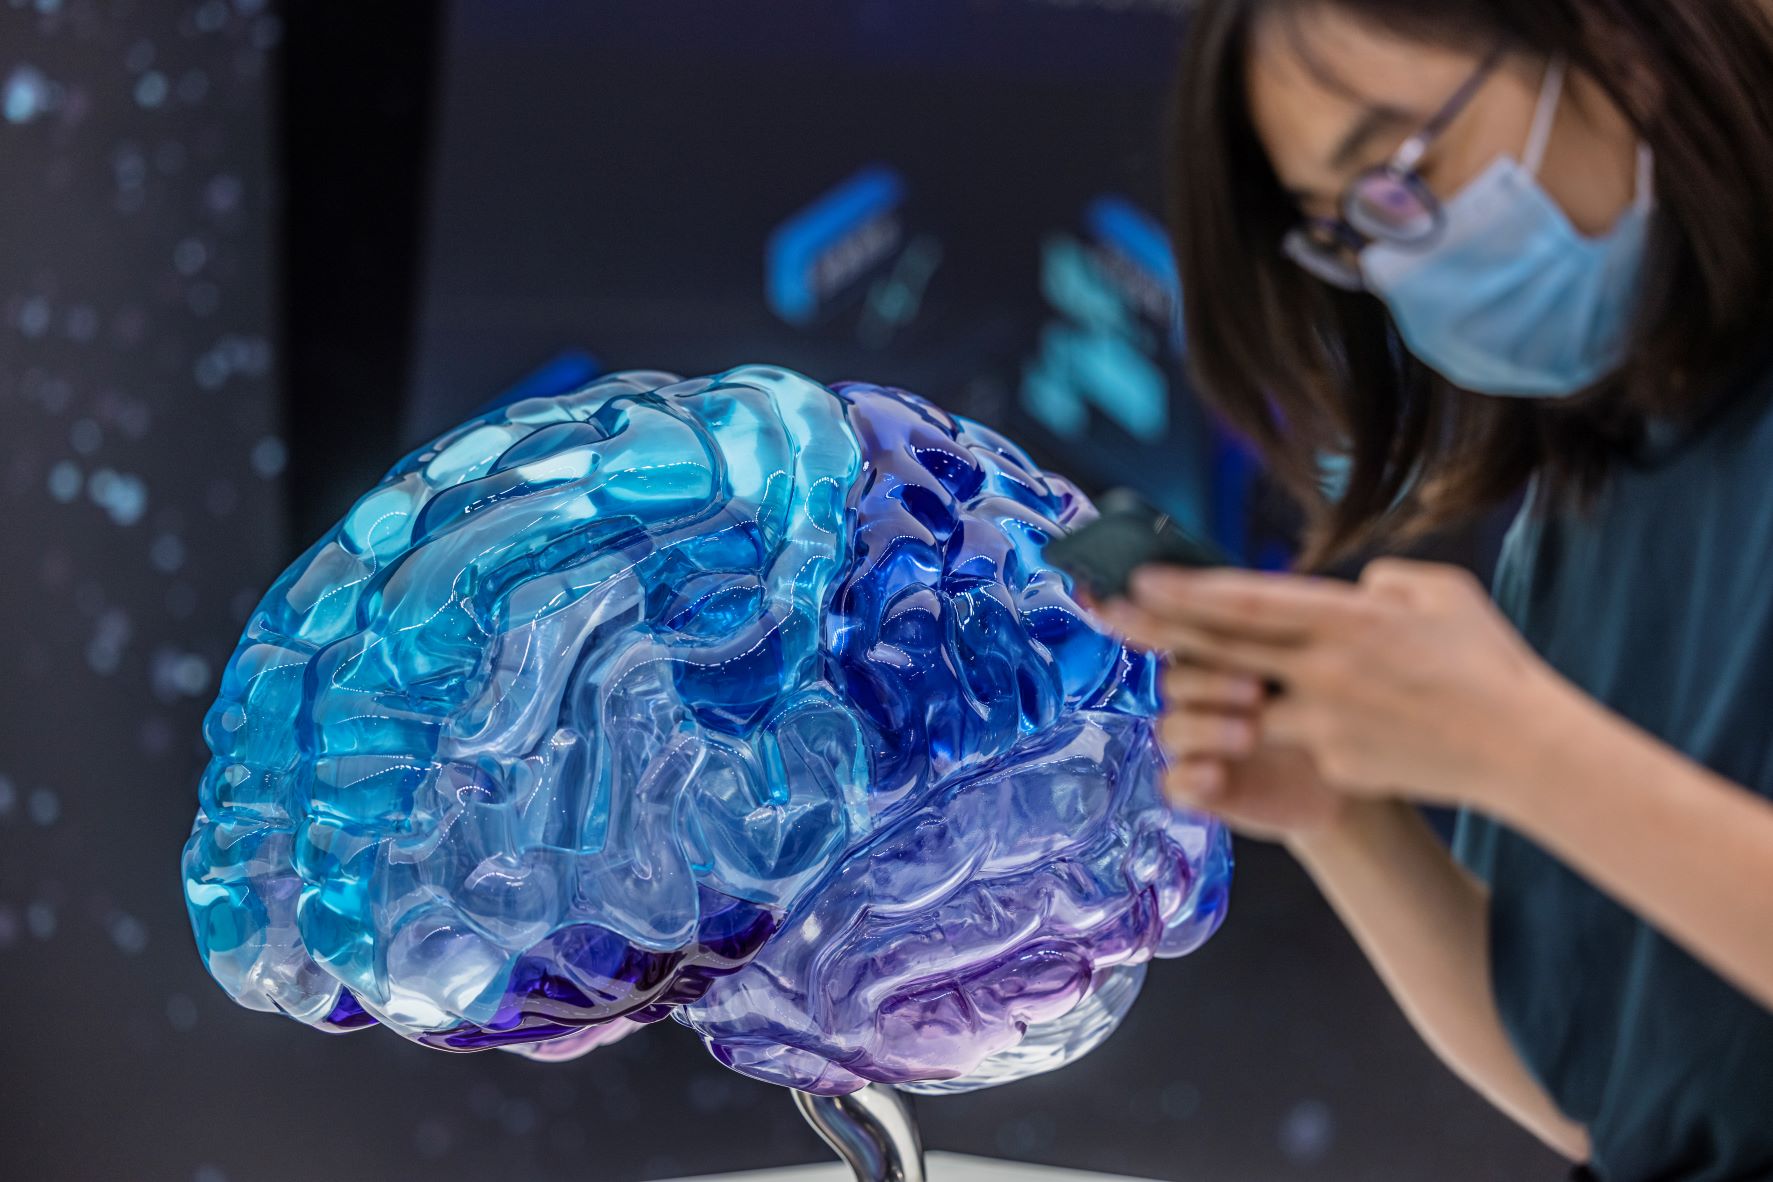

„Jedite kao da ste u Italiji na moru“: 9 saveta neurologa za svaki dan kako da sačuvate zdravlje svog mozga

Smanjenje stresa je jedan od najefikasnijih načina za zaštitu mentalnog zdravlja - međutim, i lekari priznaju, to nije uopšte lak posao.